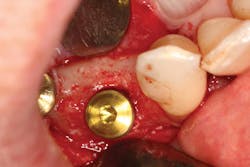

The most critical aspect of any implant system is the interface between the implant fixture and its surrounding bone (figures 1-5). Integration between the fixture and its surrounding bone is the foundation of modern implant dentistry. There is little we can do to modulate bone healing, but we can modify the implant fixture itself.

Figures 1-5: Figures 1 through 4 illustrate, respectively, a seven-year follow-up visit and a three-year follow-up visit of two different implant systems. Implant No. 22 (figure 5) shows peri-implant radiolucency following functional loading, indicating fibroencapsulation and loss of integration into bone, necessitating removal.